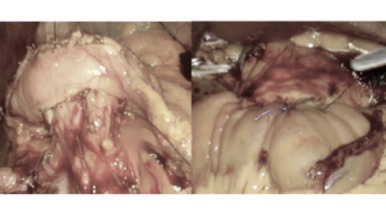

Presentamos dos casos clínicos con resección venosa del confluente espleno-mesentérico-portal seguido de una reconstrucción vascular mediante injerto antólogo de peritoneo y vaina posterior de músculo recto del abdomen.